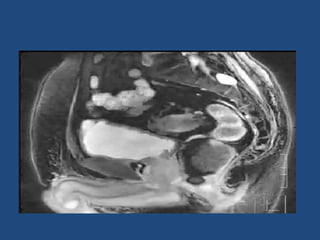

Prostate cancer is the second most common cancer globally, with varying incidence rates influenced by geography and lifestyle changes. In India, prostate cancer cases are rising due to urban migration and increased medical awareness, with current rates approaching those in Western countries. Treatment options vary by stage, including watchful waiting, surgery, radiation therapy, and hormonal treatment, each tailored to patient-specific factors.